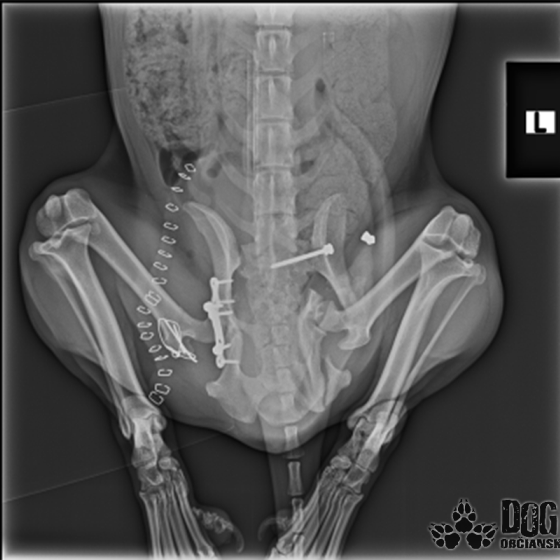

Vianoce nám klopú na dvere a mali by to byť sviatky radosti a pokoja. No u nás nebudú a pre malého Jamesa už vôbec nie. Malého Jamesa sme prijali s mnohonásobnými fraktúrami panvy. Presnejšie, s obojstrannou iliosakrálnou luxáciou/fraktúrou, viacnásobnou fraktúrou panvy, vrátane fraktúry kranialneho acetabula obojstranne. Áno, znie to hrozivo a keď si pozriete snímky z RTG, bude to ešte hrozivejšie (ďalšie snímky ešte doplníme).

Čakali ho teda štyri, veľmi náročné ortopedické operácie, takže sa musel trocha posilniť. Do starostlivosti si ho vzala MVDr. Panyi Terzieva a 17.11. mohol absolvovať prvú operáciu. V "prvom kole" krpec zvládal anestézu tak dobre, že sa rovno mohli spojiť dve operácie a tak sa celá ľavá strana dala do poriadku. Zostal samozrejme naďalej hospitalizovaný. Ďalší zákrok sa naplánoval na 20.11. a našťastie opäť všetko prebehlo hladko, a zoperovala sa celá pravá strana(nechceme sa dlho rozpisovať, prikladáme lekársku správu). James bol prepustený 24.11. ako chodiaci pacient a bez problémov ovládal aj vylučovanie! Je to priam zázrak, za ktorý opäť vďačíme MVDr. Vatolíkovi a jeho teamu.